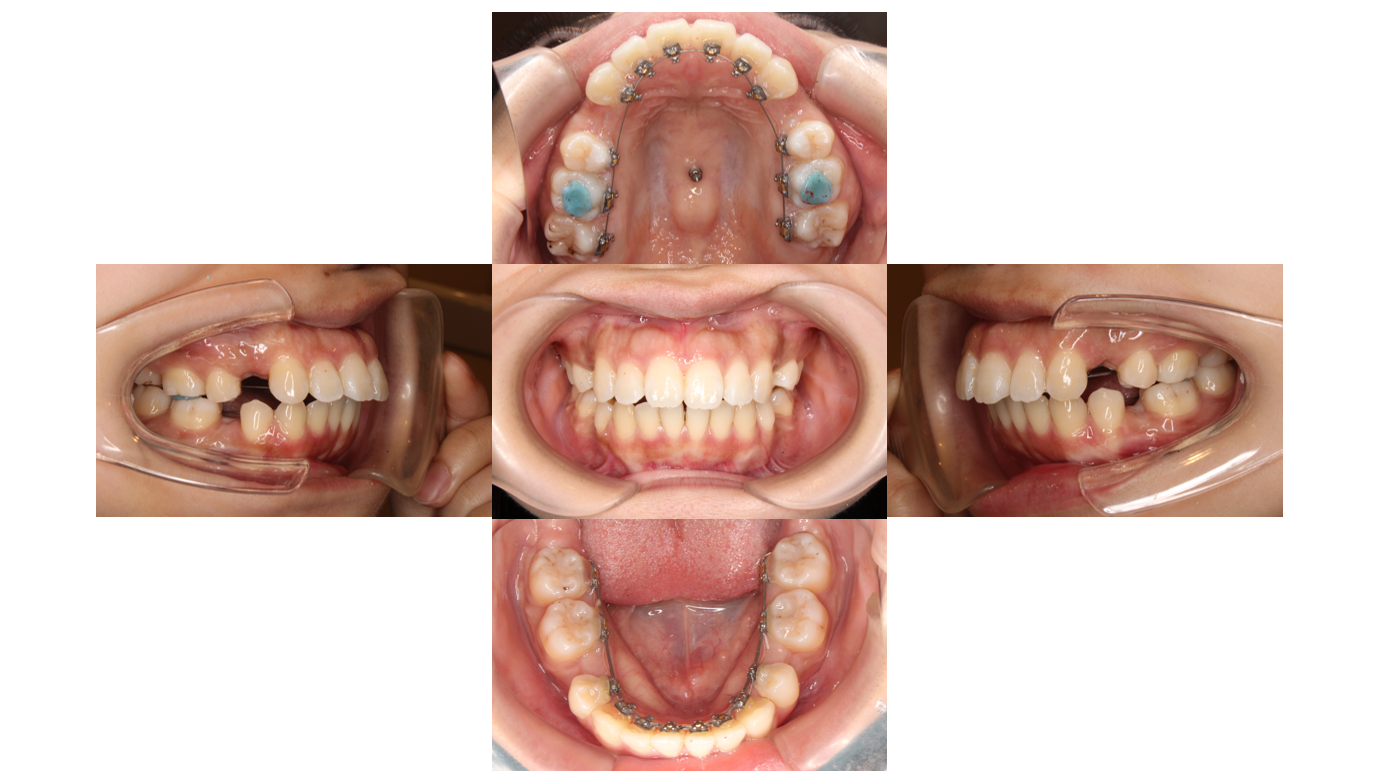

Before

初診

装置装着後

装置が裏側につきました

青い材料は歯と装置が当たらないように付与しています